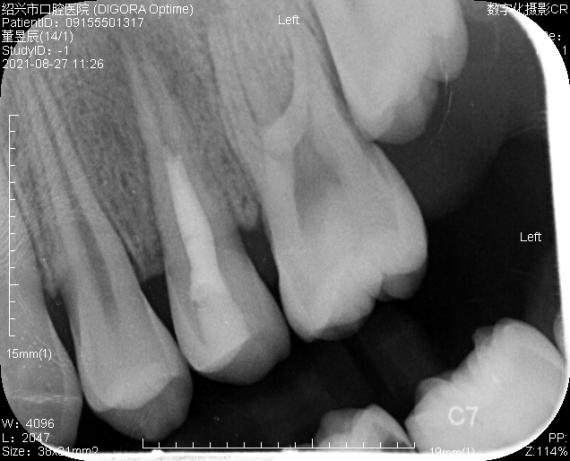

专科检查:全口口腔卫生状况可,少量软垢,25牙合面可见畸形中央尖部分磨损痕迹,松动(I°),叩痛(+),无瘘管,冷诊(- ),根尖区压痛明显。

25牙可见畸形中央尖

辅助检查:CBCT显示25牙根尖呈喇叭口样敞开,未发育完全,根尖低密度暗影。